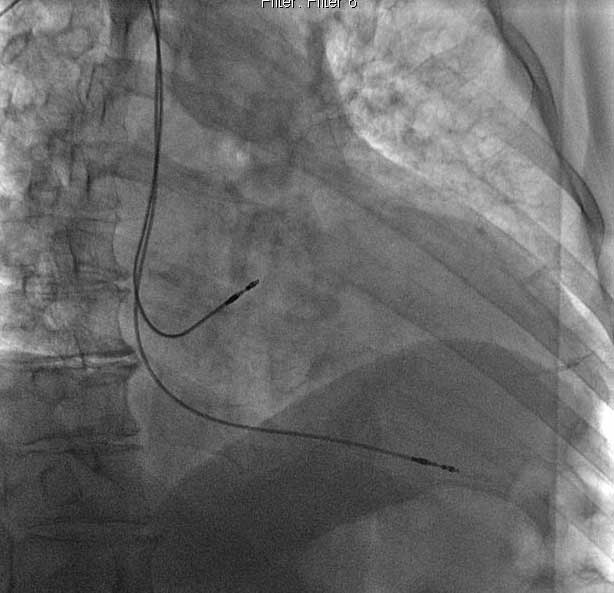

趙侃團隊ENDURITY MRI™ 雙腔起搏器植入術中

ENDURITY MRI™ 雙腔起搏器術後DSA影像